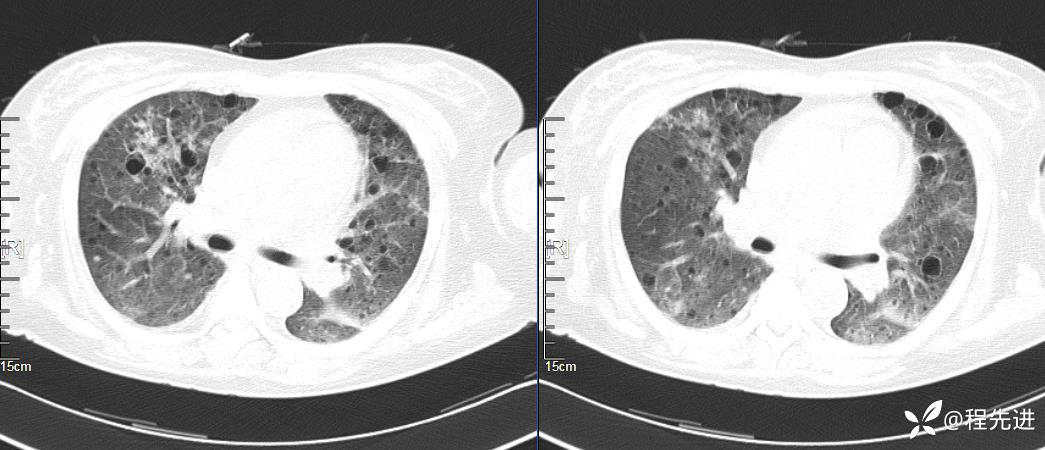

CT平扫(纵隔窗无特殊,就不上传了):

2、本例肺气囊分布有什么特点?肺气囊有无小叶核心?有没有间质纤维化及伴发结节?